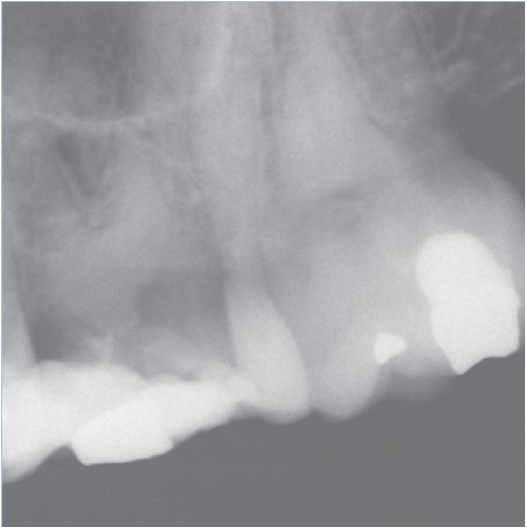

Before

Before Root Canal treatment